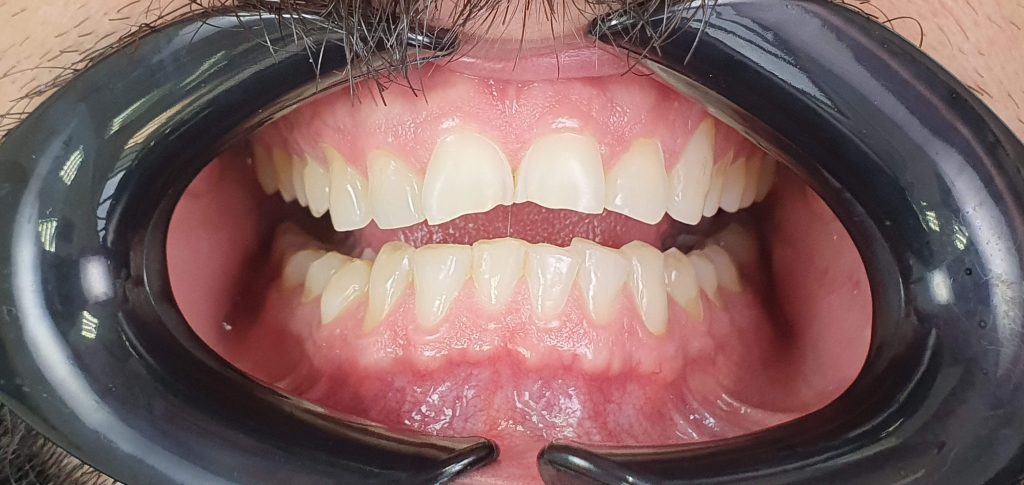

Paciente do sexo masculino, 36 anos com queixa de desgastes generalizados nos dentes. Durante avaliação clínica foi constatado desgastes devido a Biocorrosão ácida e Bruxismo.

O plano de tratamento proposto foi a realização de acréscimos em resina composta para devolver equilíbrio oclusal e estético. Uma placa interoclusal e acompanhamento médico para tratamento do refluxo gastroesofágico e dieta também foram indicados.

Para realização dos acréscimos em resina foi realizada a montagem em ASA, enceramento diagnóstico e mockup. Após a aprovação do mockup realizou-se a confecção das guias em silicone de adição transparente para técnica injetável. Nenhum desgaste para a realização dos acréscimos em resina foram realizados, a superfície foi tratada adesivamente com Clearfill SE Bond seguindo o protocolo de uso desse sistema adesivo. Os setores 1 e 2 foram os primeiros a receber os acréscimos em resina composta (Clearfill AP-X Esthetics – Flow cor B1) e na sequência os setores 3 e 4.

Posteriores inferiores finalizados

As Reabilitações utilizando resina composta injetável só é possível pois temos uma resina com propriedades mecânicas que a difere das resinas fluídas convencionais, a resina Clearfill A-PX Esthetics – Flow é uma resina nanohíbrida com 75% (em peso) de cargas inorgânicas e com excelente polimento sendo uma resina resistente e altamente estética. Além da escolha da resina, o planejamento reabilitador e as orientações ao paciente e uso da placa são de fundamental importância para a longevidade clínica desses casos. A adesão nos permite acrescentar e preservar o remanescente já tão desgastado. Essa opção reabilitadora tem sido a minha escolha, principalmente em pacientes tão jovens.